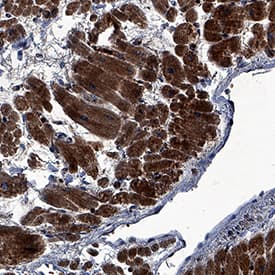

FGF-16 was detected in immersion fixed paraffin-embedded sections of human heart using Sheep Anti-Human/Mouse FGF-16 Antigen Affinity-purified Polyclonal Antibody (Catalog # AF1212) at 3 µg/mL overnight at 4 °C. Tissue was stained using the Anti-Sheep HRP-DAB Cell & Tissue Staining Kit (brown; Catalog # CTS019) and counterstained with hematoxylin (blue). Specific staining was localized to cardiomyocytes. View our protocol for Chromogenic IHC Staining of Paraffin-embedded Tissue Sections.FGF‑16 in Mouse Embryo.